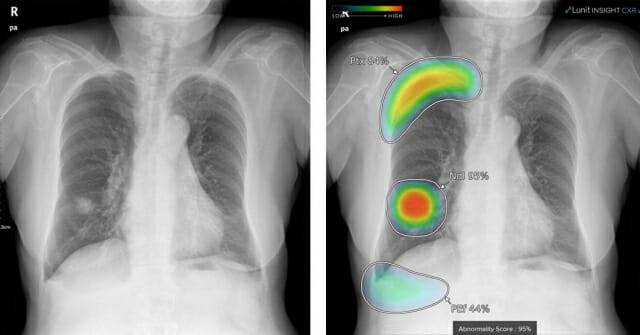

의료 영역에서는 루닛이 대표적이다. 이 회사는 흉부 엑스레이와 유방촬영술(MMG) 데이터를 분석하는 딥러닝 기반 솔루션을 개발해 왔다. 대표 제품인 '루닛 인사이트 CXR'은 세계 의학저널 '란셋 디지털헬스'에 실린 독립 연구에서 글로벌 12개 AI 솔루션 중 결핵 검출 능력 1위를 기록했다.

민감도 90% 기준에서 특이도 67.7%로 세계보건기구(WHO) 목표에 가장 근접했고 특이도 70% 기준에서도 민감도는 89.5%에 달했다. 개발도상국에서 여전히 주요 사망 원인인 결핵 진단에 최적화된 성능이다. 루닛 AI는 현재 유럽, 중동, 아시아 등 500여 개 병원에 도입돼 있다. 의료진 판독 시간을 36% 줄였고 암 발견율을 15% 이상 끌어올렸다는 임상 결과도 보고됐다.